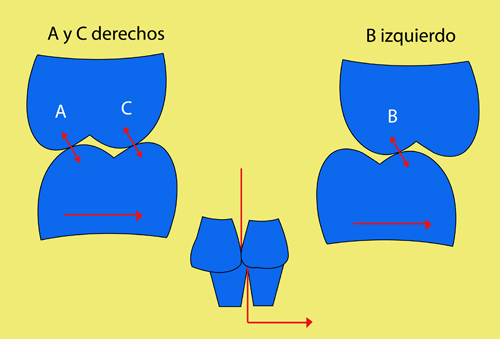

En ciertas áreas del saber humano, el lenguaje confuso o criptográfico Muchas son las técnicas elaboradas para lograr un desgaste selectivo, y numerosos autores han expuesto en su momento variadas formas de lograr una función oclusal fisiológica mediante el ajuste de la misma. Han pasado años desde entonces y, sin embargo, aún hoy, un altísimo porcentaje de profesionales “navega” por el mar de la confusión oclusal, dada la diversidad de conceptos y escuelas, sin lograr arribar a costa alguna donde poder anclar un conocimiento sólido sobre cómo tratar la oclusión Ya se esté realizando una simple obturación, endodoncia, incrustación, radectomía u ortodoncia, la lógica pocas veces, en la mayoría de los casos, vincula un tratamiento con otro, siendo el resultado final el mismo caos inicial; enmascarado por mucho tratamiento profesional. El ajuste oclusal es un medio inicial de proveer al sistema enfermo de: Dicha técnica, que puede ser terapéutica en sí misma; consta de dos etapas, a saber: 1) Ajuste Oclusal por Adición Mediante el estudio de la guía anterior, encargada de efectuar las Disclusiones durante las excursiones mandibulares, podremos observar si ésta es funcional o no. • Marcas de carácter continuo, si en ese recorrido se produce la Disclusión de los sectores posteriores y todo marcha correctamente. FIG 1-2 Si por el contrario observamos: • Marcas de carácter discontinuo, significa que dicha Disclusión se está efectuando por medio de una pieza dentaria posterior a la guía anterior. FIG 3-4-5 (FIGS. 3, 4 Y 5). En la figura 6 las flechas indican, en un caso clínico de análisis oclusal, la presencia de marcas discontinuas que indican Interferencias en Propulsiva. FIG 6-7 Y por último, si existieran: • Abrasiones de las áreas discluyentes en las áreas de diagnóstico de la guía anterior, deberemos aportar material a dicha zona para no permitir el choque lateral de las piezas posteriores (Ajuste Oclusal por Adición) En las imágenes 11 y 12 podemos observar la adición de composite en la punta de un canino derecho, previa la observación de la Faceta Parafuncional remarcada durante el análisis oclusal en el articulador. (FIGS. 8 A 12). 2) Ajuste oclusal por Sustracción o Desgaste Habiendo cumplido ya con la verificación de la funcionalidad de la Guía Anterior, comenzamos los desgastes en céntrica, a fin de lograr un único arco de cierre, guiado eficazmente por la Guía Anterior; es decir: la coincidencia entre Oclusión Habitual y Oclusión en Relación Céntrica. En este caso, intentar gastar dichos puntos, de ser posible sólo en las cúspides de corte o no fundamentales: • Crestas Triangulares Internas, Cúspides Vestíbulares Superiores • y un poco de las Crestas Triangulares Internas, Cúspides (FIGS. 13 A 16). Si la deflección es hacia el lado opuesto, se invierten los desgastes. En las migraciones hacia adelante, las únicas razones posibles están en los puntos estabilizadores (FIG. 17); es decir: -Vertientes Distales de los Rebordes Marginales, Triangulares (FIG 17) (FIG 18 A-B-C-D) Obsérvese cómo, en una boca prácticamente entera, comienzan a “desmoronarse” prismas adamantinos (FIG. 19), como consecuencia de un punto prematuro de contacto, ubicado en la posición de un estabilizador, que provoca la discrepancia horizontal postero-anterior causante de dicho efecto (FIG. 20). FIG 19-20 Dicho punto, será necesario ajustarlo antes de cualquier tratamiento en la zona ¿Cuáles serían las consecuencias si esos incisivos fueran implantados tal como es frecuente observar en múltiples congresos y cursos de implantología, donde el tema de la oclusión no es más que un cuadro polifacético y anecdótico? 14 15 16 17 Todo producto del adelantamiento mandibular Realizados ya los desgastes en céntrica, obteniendo de esta manera un único arco de cierre, es decir, oclusión en relación céntrica, debemos realizar el ajuste de las excéntricas, apoyando la acción de la guía anterior, para lo FIG 22 a. De un lado a otro de un mismo maxilar, la imagen es especular, o sea invertida. b. En hemimaxilares cruzados, la imagen es idéntica. Allí donde existan colisiones entre cúspides, se deberá crear un surco para que dicha cúspide antagonista migre a su través, tanto en el lado de no trabajo, como en el de trabajo y en el de propulsión. FIG 23 Es importante conservar esta parte del surco, ya que si no existieran, los contactos entre cúspides serían en superficie y no puntiformes (fig. 24). FIG 24 1. Obtener un único arco de cierre con coincidencia entre oclusión habitual y relación céntrica. 2. El cierre mandibular debe ser recibido sólo por la tabla premolar-molar. 3. Durante las excursiones funcionales es la guía anterior la que debe sufrir las fuerzas laterales. 4. De cumplirse estas dos premisas debemos obtener libertad de desplazamiento (no confundir con libertad en céntrica) a las piezas posteriores mediante la creación de surcos disclusivos. Examinadas ya las posibles migraciones mandibulares y los desgastes o aposiciones necesarios para poder ocluir en céntrica, es fundamental recordar que, previamente a todo tipo de ajuste, se ha hecho necesario ubicar a la mandíbula en relación céntrica. Para ello debemos utilizar el propio funcionalismo muscular 22 FIG 25 Y esto no significa otra cosa que: piezas dentarias estables en todos los planos del espacio, ATM centrada en la cavidad glenoidea, periodontos sin tensión, músculos en la dimensión de elongación adecuada para un fisiologismo Paz absoluta en la intimidad del Sistema Estomatognático. Y así, como corolario final, es posible establecer una regla de oro similar en importancia a la conocida formula: Forma = Función Ésta es: FIG 26 FUNDAMENTOS NEUROFISIOLÓGICOS DEL REGISTRO DE OCLUSIÓN EN RELACIÓN CÉNTRICA ( ORC) MEDIANTE EL USO DE LAMINILLAS DE LONG CUADRO

Si la deflección es por ejemplo hacia la izquierda, observaremos que las únicas causas posibles son por contacto en los puntos de estabilidad vestíbulo-palatina A o C derechos o bien en el B izquierdo.

Es decir:

(Punto A) y Crestas Triangulares Internas, Cúspides Linguales Inferiores (punto C), del lado derecho.

Estampadoras (punto B), del lado izquierdo .FIG 13-14-15-16